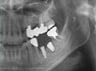

08.01.15 처음 내원 때, 사진

: 타 병원에서 임플란트 2개를 심었는데,

후방의 하나는 빠져버렸고, 전방 부위에도

잇몸뼈의 손상이 컸음.

그래서, 제거 수술 후 인공뼈이식을 통해,

잇몸뼈를 재생시킨 후,

2개의 임플란트 재식립을 계획하였다.